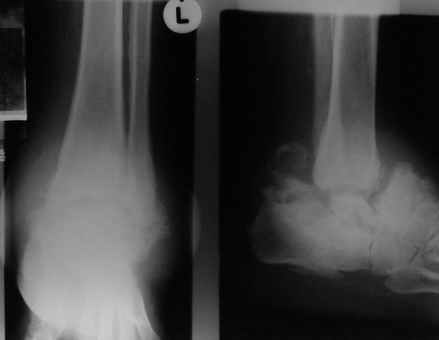

Уажаемые коллеги, представленные рентгенограмммы я показывал на нашем х-рей митинге - они были встречены с большим интересом.. Ну, ещё бы - я сам эту патологии встречал раза три за всю свою долгую жизнь:

После меня выступал с новыми находками для своей коллекции Эмануэл Лакью Тесема, хирург-ортопед из Эфиопии: Мне понравились его находки:

Кто шустрый - при какой патологии встречается так называемые "суставы Шарко"? Второе приобретение доктора Эмануэла мне понравилось своим романтическим названием: Candle bone - <кость-в-виде-оплывающей-свечи> : Просто редкая патология: